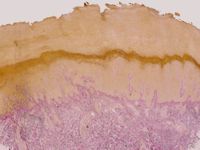

Diagnostiek:Biopt, speciaal vragen om mucine kleuring

en de DD vermelden. De patholoog kan bij mucine deposities aanvullend onderzoek

doen naar de herkomst er van (keratine, immunoglobuline).